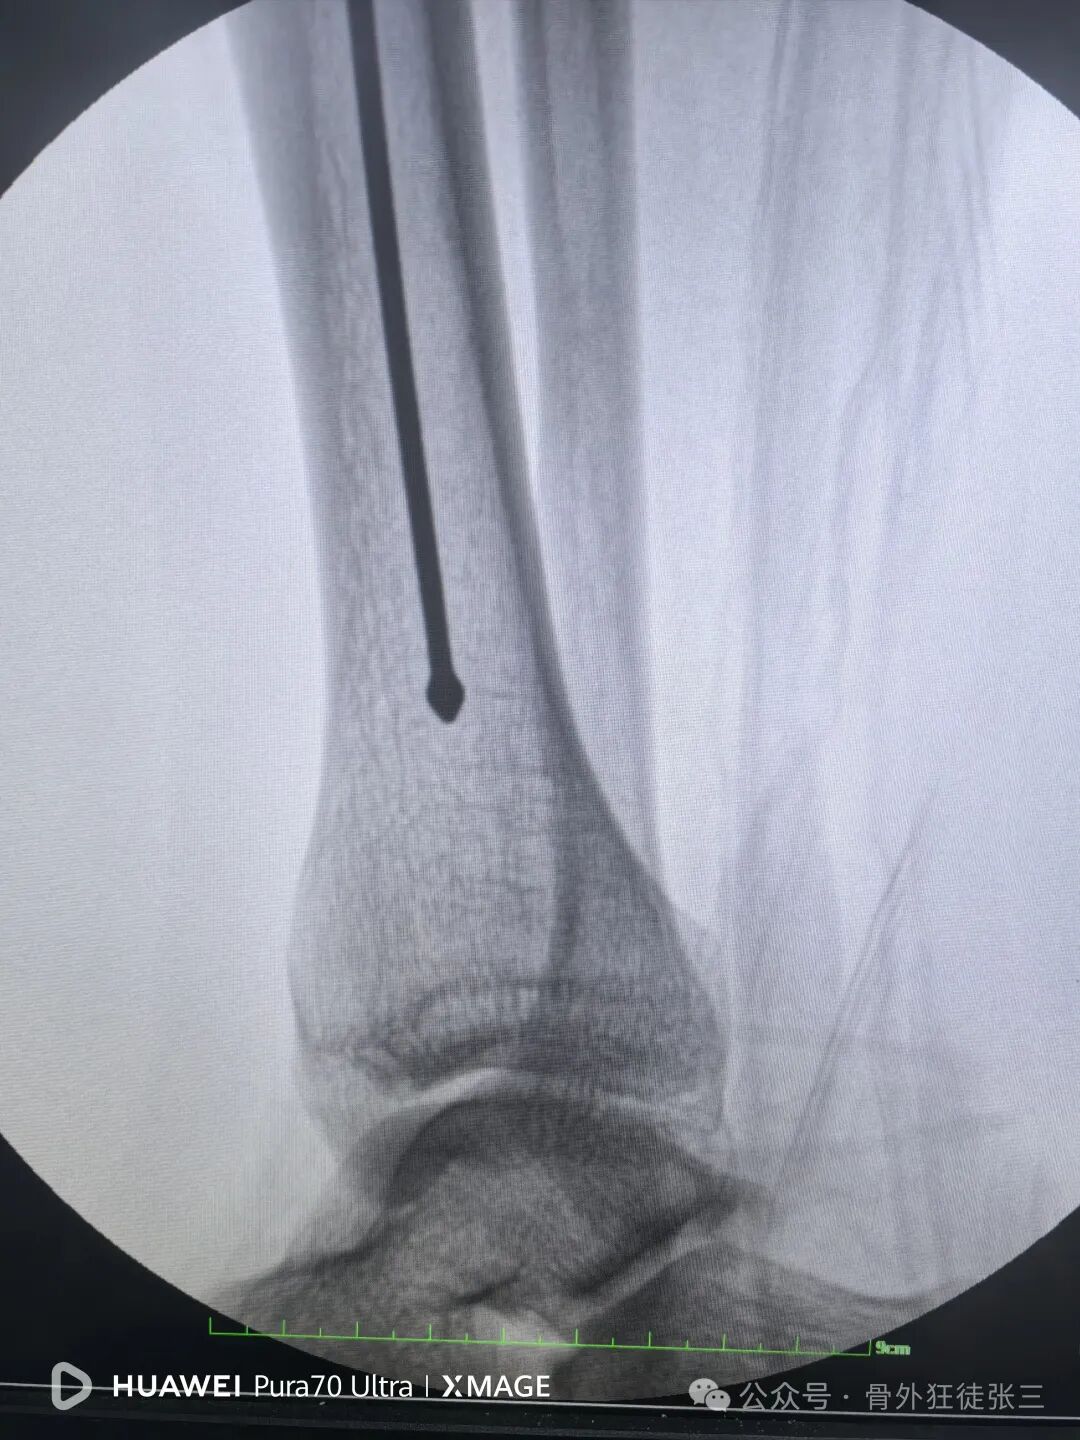

侧位复位良好

踝关节侧位钉子长度满意,居中